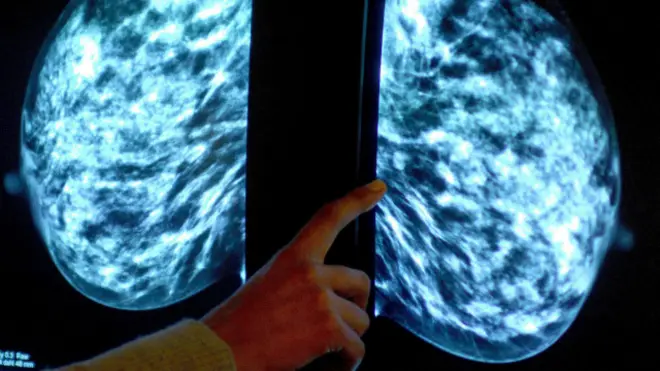

इस अध्यन से पता चला कि लंबे लोगों को कैंसर होने की आशंका ज़्यादा होती है जिनमें ब्रेस्ट कैंसर और त्वचा कैंसर प्रमुख है.

लंबे लोगों को कैंसर का ख़तरा ज़्यादा